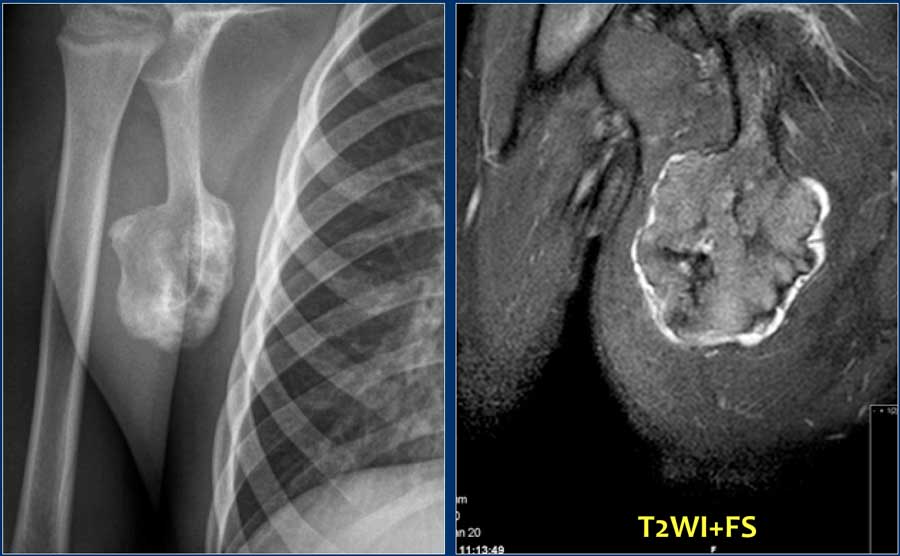

Here images of a 30-year-old male.

There is a wel-defined lytic lesion of the olecranon with several ridges and a pathologic fracture.

The differential diagnosis includes giant cell tumor and ABC.

The T2WI+FS shows fluid-levels due to sedimentation making ABC the most likely diagnosis.

Biopsy however revealed Brown tumor.